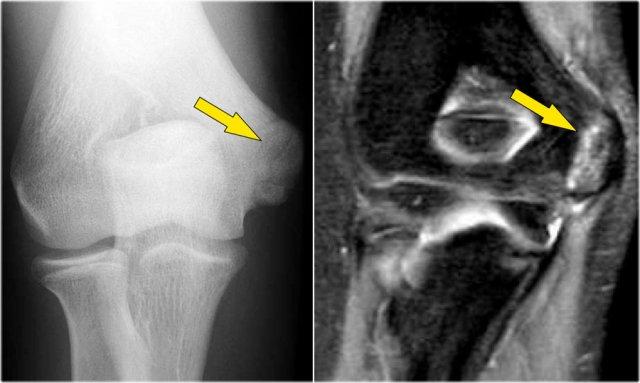

Hình chụp X-quang của một vận động viên bóng chày 15 tuổi với tiền sử đau khuỷu tay 4 năm và gần đây có triệu chứng kẹt khớp.

Có một vùng thấu quang khu trú ở chỏm con và một số mảnh vỡ.

Đây là hình ảnh điển hình của tổn thương sụn xương chỏm con và hiện tượng kẹt khớp có thể là kết quả của các dị vật trong khớp.

Continue with the MR…

MR-arthrogram xác nhận tổn thương sụn xương.

Có gadolinium nằm giữa xương cánh tay và tổn thương sụn xương, cho thấy tổn thương này không ổn định.

Nếu không có gadolinium, hãy tìm dịch khớp chui xuống dưới mảnh sụn xương.

Có một mảnh thể tự do trong ngách sau của khớp quay-cánh tay.

Notice also the fragmentation as seen on the axial image.